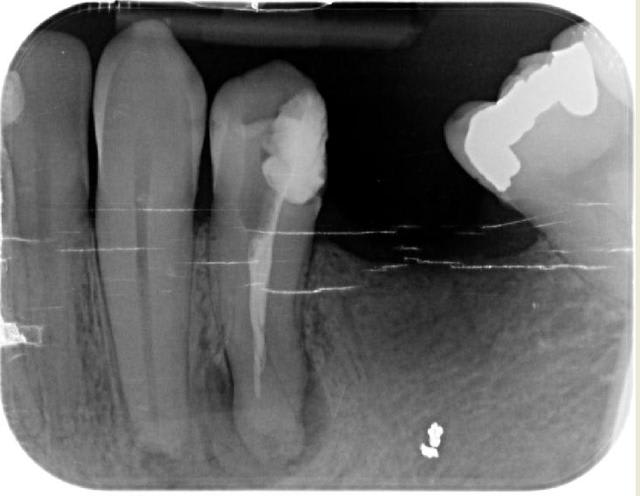

fouilla

pour déterrer ce post je vous mets un zoli sapin de noël en avance

bon allez je baisse les bras, maintenant il faut même une photo d'un champ

par provoc on s'est amusé à faire une photo

pour répondre à la question avec quoi j'obture : maitre cone et condensation verticale simplement

cadeau (si je puis me permettre) de fin

mon objectif avait été de dire qu'on pouvait aussi faire simple mais la critique SYSTEMATIQUE me casse les c...